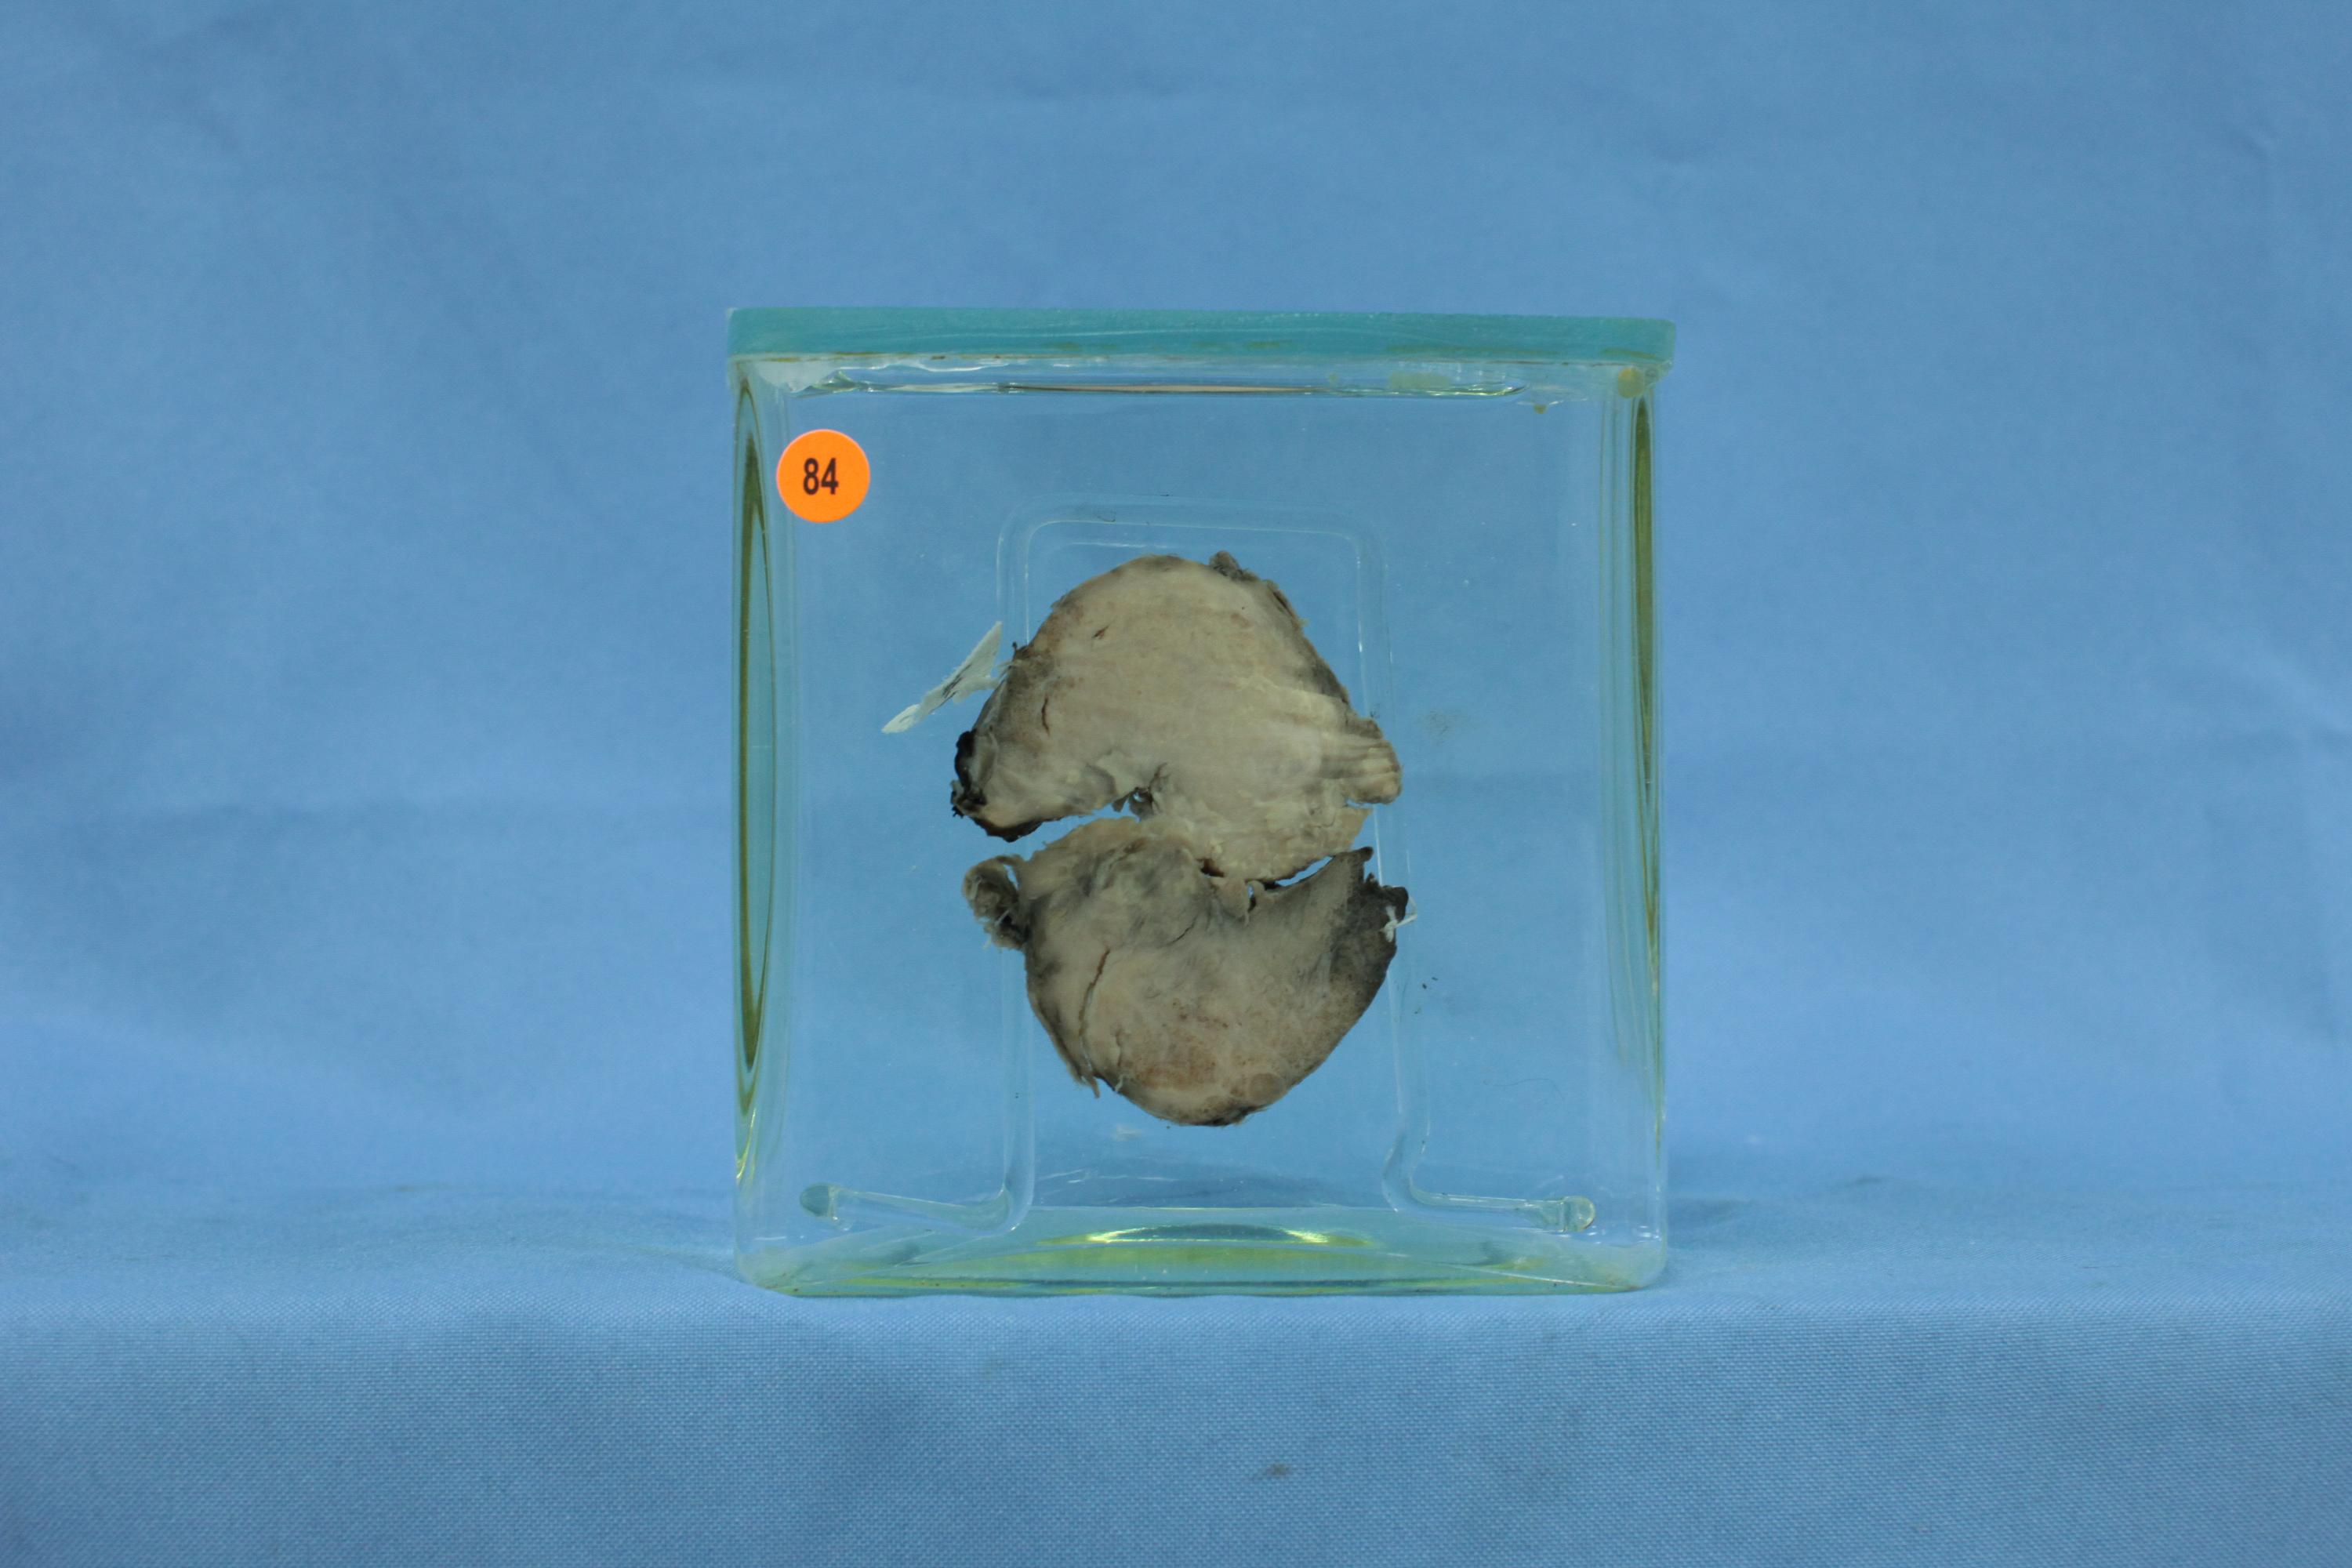

内分泌-73-84. 胸腺瘤

标本为胸腺组织,切面见一灰黄色结节,直径约5cm,质实,包膜完整,伴少量点状坏死。